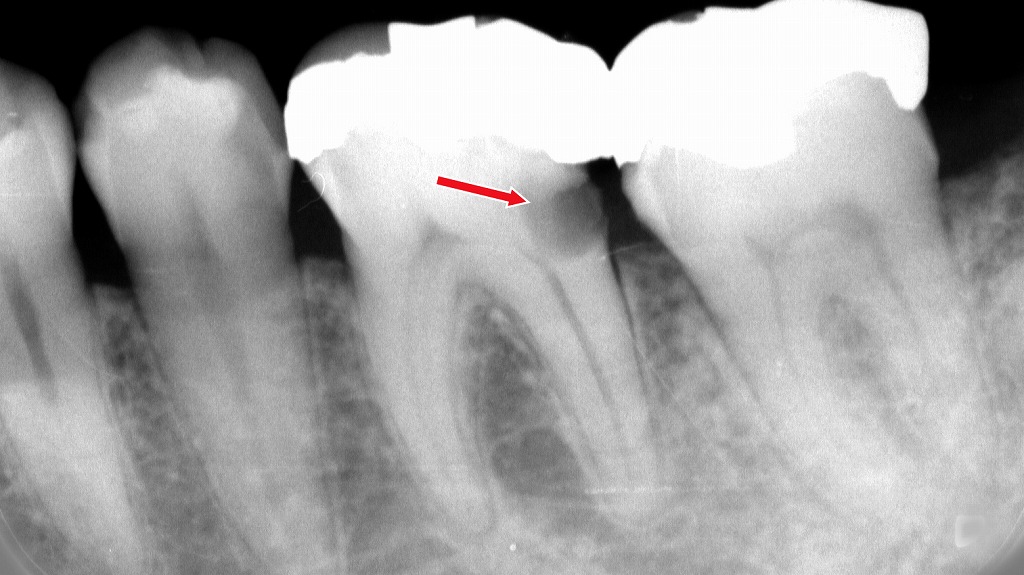

赤矢印の部位は、奥歯同士の接触面から虫歯が進行し、内部で神経(歯髄)付近まで達している状態です。見た目では気づきにくい“隣接面カリエス”は、噛んだときの痛みやしみる症状、さらには歯髄炎を引き起こす大きな原因になります。噛むと痛い場合は、神経の保存が可能かどうかを早期に判断することが重要です。